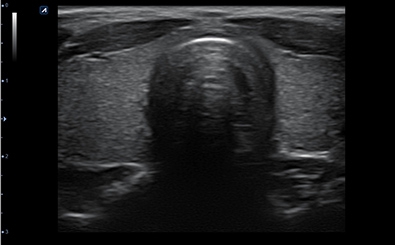

CLINICAL IMAGES

臨床影像

Thyroid